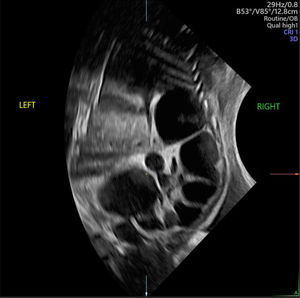

El diagnóstico diferencial de DTU depende en gran medida de la localización y del grado de dilatación dentro del tracto urinario. La hidronefrosis sin hidrouréter puede indicar una obstrucción de la unión pieloureteral (UPU) (fig. 4), mientras que la dilatación de la pelvis renal con hidrouréter sugiere más probablemente un reflujo vesicoureteral (RVU) o una obstrucción de la unión vesicoureteral (fig. 5). Además, una hidronefrosis severa puede, en ocasiones, simular RDMQ; por lo tanto, este último debe incluirse en el diagnóstico diferencial. Dado que un sistema colector renal duplicado puede asociarse con hidronefrosis en una o ambas porciones, se recomienda una evaluación detallada del aspecto renal y la búsqueda de un ureterocele en la vejiga. La dilatación de todo el sistema (riñón, uréter y vejiga) indica una obstrucción congénita del tracto urinario inferior (fig. 6), que puede tener diversas etiologías, como válvulas de uretra posterior (en fetos masculinos), atresia uretral o malformaciones cloacales (en fetos femeninos)19. Con excepción de la pielectasia transitoria, siempre se ofrece evaluación genética prenatal ante la sospecha de DTU fetal.

Hidronefrosis sin hidrouréter del riñón izquierdo alrededor de las 20semanas de edad gestacional. El riñón superior (izquierdo) muestra dilatación pélvica y caliectasia, mientras que el riñón inferior (derecho) presenta un aspecto normal. Imagen ecográfica del Centro Médico de la Universidad Erasmus.